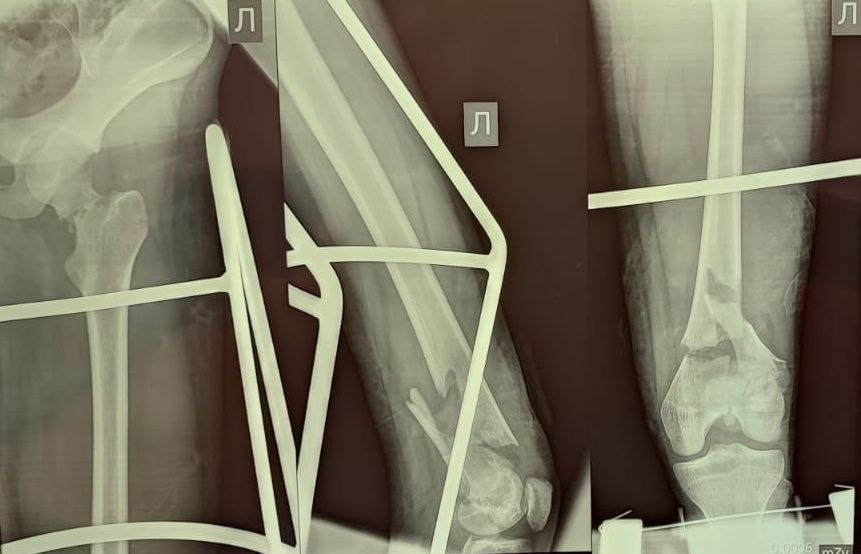

Пятнадцатилетняя школьница провела несколько месяцев в аппарате Илизарова после падения с высоты пятого этажа. Девочка поскользнулась, когда пыталась вместе с сестрой-близняшкой выбраться через окно из горящего здания. В городской детской клинической больнице

— Здесь беда была в чем. Шейка бедра была сломана — а это то, за счет чего мы вообще опору даем и благодаря чему есть движение в тазобедренном суставе. Плюс оскольчатый перелом был в дистальном отделе, где коленный сустав. Было большое количество отломков, нужно было всё застабилизировать. Был риск несращения, так как идет размозжение тканей вокруг. Был велик риск асептического некроза — когда кости не приживаются, — цитирует Минздрав Омской области врача — травматолога-ортопеда Максима Перфилова.

Но всё закончилось хорошо. Аппарат для сращения костей уже сняли, и, как сообщили в пресс-службе ведомства, девочка ходит сама, не испытывая боли. Сестра в тот день не пострадала — ее спасли из задымленной квартиры пожарные.